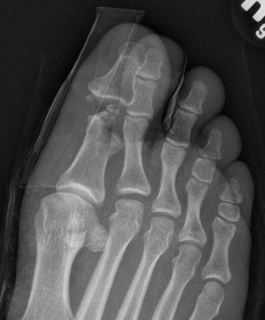

Blocks to closed reduction

Capsule / plantar plate

Sesamoids

Inter-sesamoid Ligament

Open Reduction

Dorsal approach

- protect dorsal superficial nerve (branch of SPN)

- divide capsule medial to EHL

Reduce and repair plantar plate / bipartite sesamoid

+/- K wire

Surgical approach to 1st MTPJ dislocation